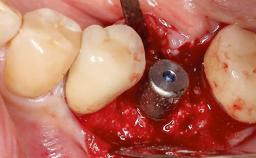

Peri-Implantitis Modified by the Presence of Submucosal Excess Cement: Reconstructive Therapy and a Ten-Year Follow-up

This case outlines the reconstructive therapy by Giovanni Salvi resulting in defect fill and inflammation-free peri-implant soft tissues at 10-year follow up. This case highlights the importance of regular monitoring of implants during supportive therapy.

A 30-year-old female patient was referred to the Department of Periodontology of the University of Bern, Switzerland, by a private dentist. Tooth 45 was congenitally missing and had been replaced with an implant three years prior to the first visit at the Department of Periodontology.